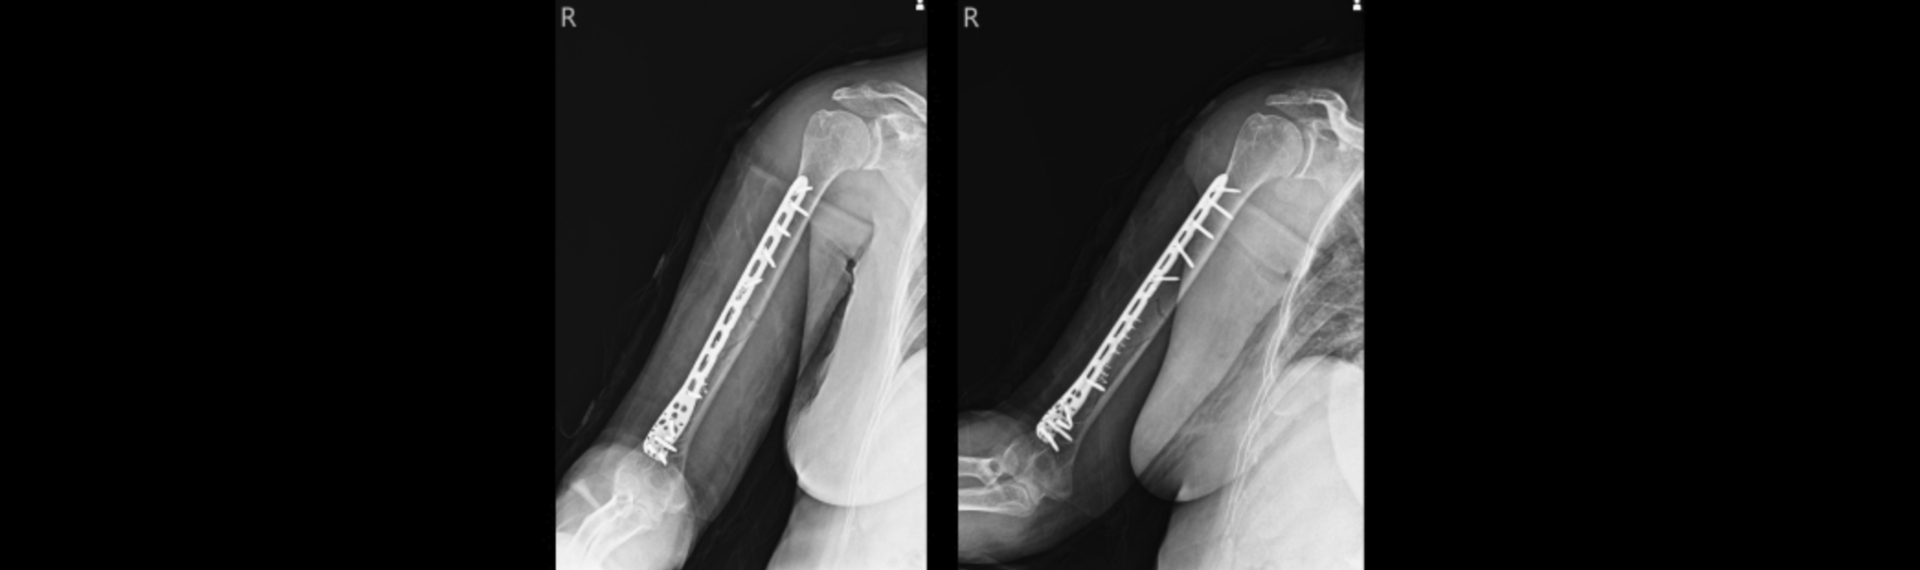

상지골절

상지골절은 상지(어깨부터 손가락까지 총 64개 뼈로 구성된 부분)에 강한 외력이 작용하여 부분적으로 또는 완전히 엇나가 뼈의 연속성이 소실된 상태를 말합니다.

상지골절 치료방법

골절의 치료는 응급 치료, 본 치료, 재활 치료의 절차로 진행됩니다.

응급 치료는 부목 고정으로 추가적인 연부 조직 손상을 예방하고, 통증을 경감시키며, 환자의 엑스레이 검사를 용이하게 하는 목적으로 시행됩니다.

골절의 본 치료는 환자의 전신 상태가 안정된 후에 시행되며 손상 정도, 부위 및 합병증의 유무에 따라 세부적 치료 방법을 선택합니다.